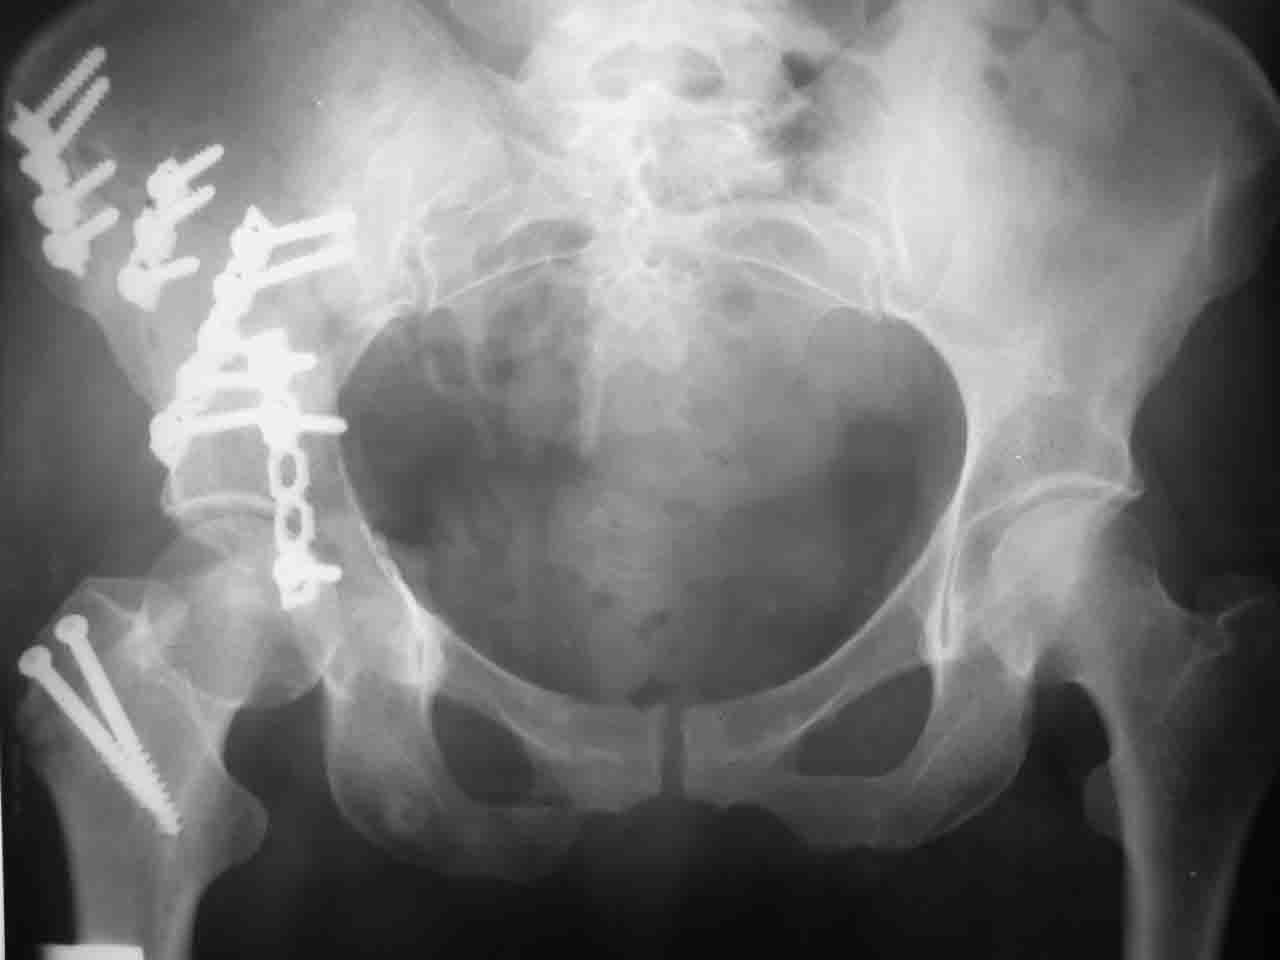

Re: Перелом вертлужной впадины

Смирнов Алексей 09 Ноябрь 2004, 01:17

Снимки и схема